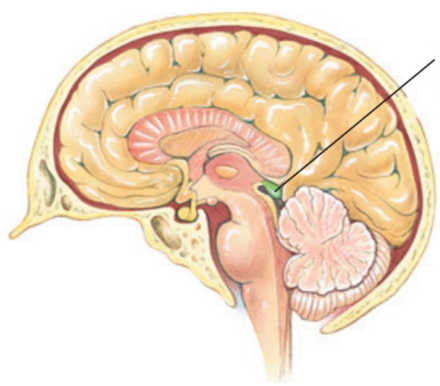

Name this gland

The pinneal gland- part of the epithalamus, posterior to the thalamus